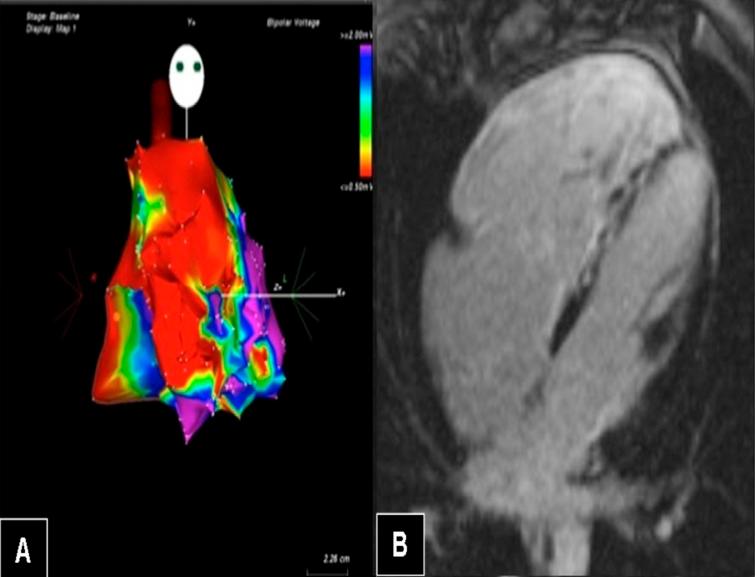

Science and practice of arrhythmogenic cardiomyopathy: A paradigm shift.

Glob Cardiol Sci Pract. 2013 Nov 1;2013(1):63-79. doi: 10.5339/gcsp.2013.8. eCollection 2013.